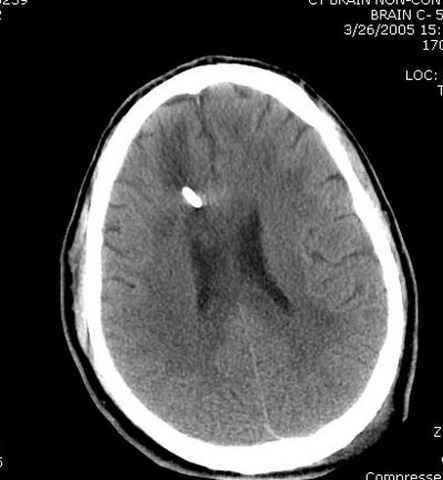

Наблюдается службой травмы и нейрохирургии (ICP) Increased Intracranial Pressure by ventricular cateter

постоперационные

монииторинг